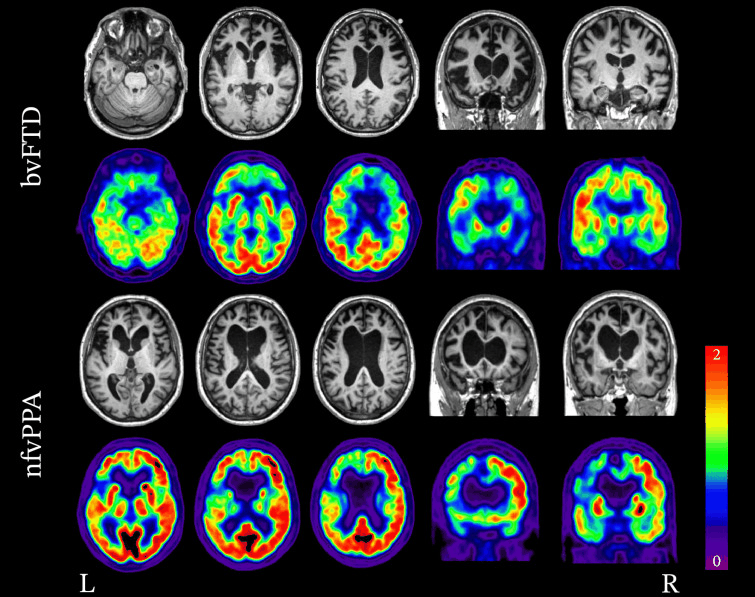

Padrões de neuroimagem associados à variante comportamental da DFT (vcDFT) e à variante não fluente da afasia progressiva primária (vnfAPP). RNM estrutural e FDG-PET demonstrando a variabilidade nos padrões de atrofia e hipometabolismo na DFT. No caso da vcDFT, observa-se atrofia bilateral significativa e hipometabolismo no lobo frontal. No caso da vnfAPP, a atrofia e o hipometabolismo são lateralizados e afetam muito mais o lobo frontal esquerdo do que o direito.

Peet BT et al. Neurotherapeutics 2021 Abr; 18 (2): 728-52; usado com permissão